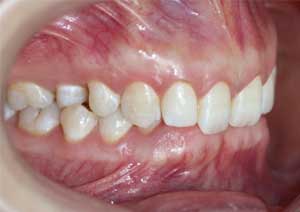

La supraclusion est définie comme le recouvrement excessif des incisives mandibulaires (inférieures) par les incisives maxillaires (supérieures).

Cliniquement, cela signifie qu’au sourire, le patient ne laisse pas apparaître les dents inférieures.

Il s’agit d’un problème de dimension verticale, fréquemment rencontré en pratique orthodontique quotidienne.

Avant